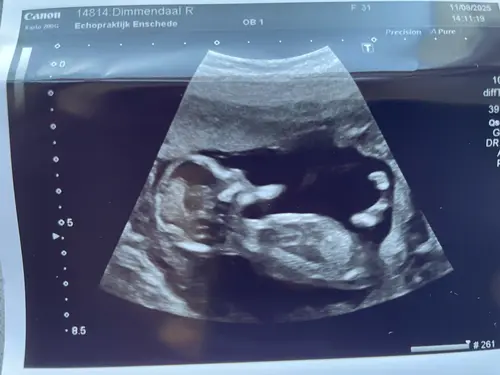

Ik ben heel benieuwd wat jullie hiervan kunnen maken! Het maakt me niet uit wat het wordt, maar ik ben zo enorm nieuwsgierig! Deze echo is gemaakt bij 13 weken en 0 dagen. Hopelijk kunnen jullie er wat theorieën op loslaten! ☺️

Als ik goed naar dit echo-beeld kijk, lijkt de nub wat meer horizontaal/parallel aan de ruggengraat te liggen, niet sterk omhoog gericht. Volgens de NUB-theorie zou dat meer richting meisje wijze